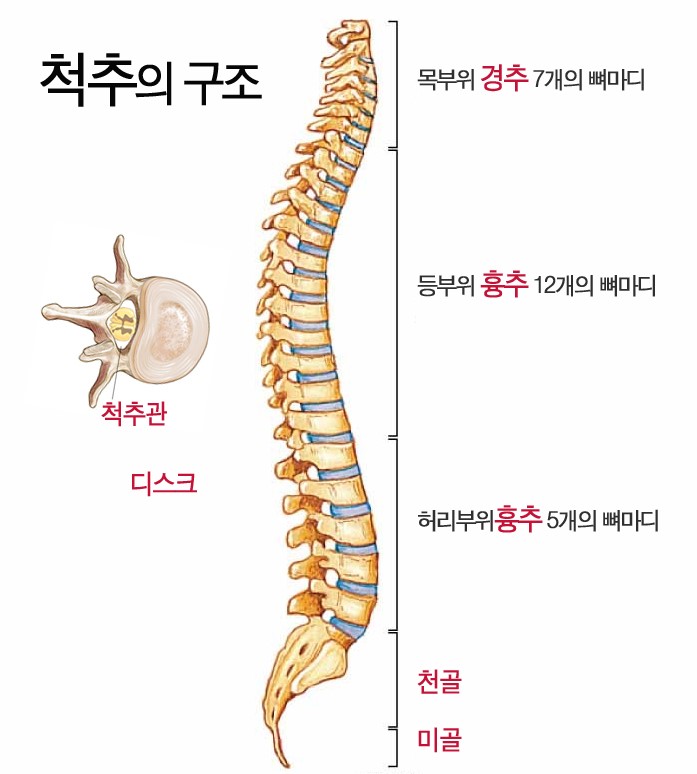

맹기호의 요추 x-ray 사진이다.

맹기호의 요추 x-ray 사진이다.